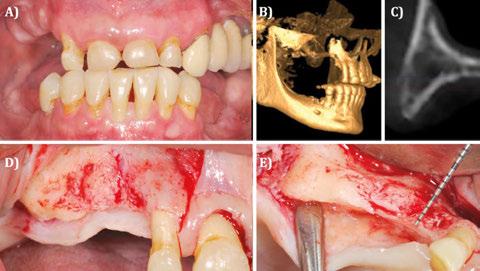

Figura 9. Caso clínico con membrana reabsorbible.

A) Situación clínica basal. B) Sondaje a través de la fístula en basal. C) Situación radiográfica basal (2D). D) Situación radiográfica basal en posición de 24 (3D). E) Situación radiográfica basal en posición de 25 (3D).

Figura 11. Caso clínico con membrana reabsorbible (ZMATRIX™). Continuación. A) Eliminación del tejido de granulación y visualización del defecto óseo vestíbulo-palatino. Vista vestibular. B) Eliminación del tejido de granulación y visualización del defecto óseo vestíbulo-palatino y el lecho alveolar posextracción. Vista oclusal. C) Estabilización de la membrana (ZMATRIX™) en el colgajo palatino. D) Utilización de injerto óseo alogénico particulado (OraGRAFT 70/30 Aloinjerto 70% min / 30% desmin) para la reconstrucción del defecto óseo. Vista vestibular.

10. Caso clínico con membrana reabsorbible. Continuación. A) Primer procedimiento quirúrgico. Incisión biselada a un diente de distancia del área a reconstruir. B) Liberación del colgajo. C) Liberación del colgajo. D) Extracción del diente en posición de 25 por fractura.

Figura 12. Caso clínico con membrana reabsorbible (ZMATRIX™). Continuación. A) Utilización de injerto óseo alogénico particulado (OraGRAFT 70/30 Aloinjerto 70% min / 30% desmin) para la reconstrucción del defecto óseo. Vista oclusal. B) Adaptación de la membrana reabsorbible (ZMATRIX™) cubriendo el injerto óseo. C) Sutura y cierre primario avanzando el colgajo coronalmente. D) Situación radiográfica (2D) inmediata postoperatoria.

Figura 13. Caso clínico con membrana reabsorbible.

Continuación. A) Situación clínica tras 4 meses de cicatrización. B) Situación radiográfica (3D) en posición de 24.

C) Situación radiográfica (3D) en posición de 25.

D) Colgajo a espesor total. Vista oclusal.

E) Colocación de implantes en posiciones 24 y 25.

Figura 14. Caso clínico con membrana reabsorbible. Continuación. A) Injerto de tejido conectivo en vestibular de los implantes. B) Sutura del injerto de tejido conectivo.

C) Radiografía (2D) inmediata posoperatoria.

D) Cicatrización tras 3 meses de cicatrización.